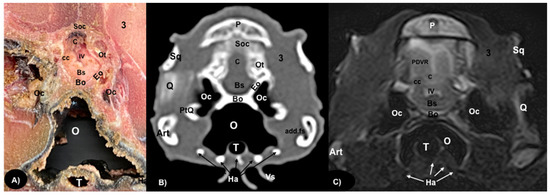

3.1. Anatomical Sections

3.2. Computed Tomography (CT)

3.3. Magnetic Resonance Imaging (MRI)